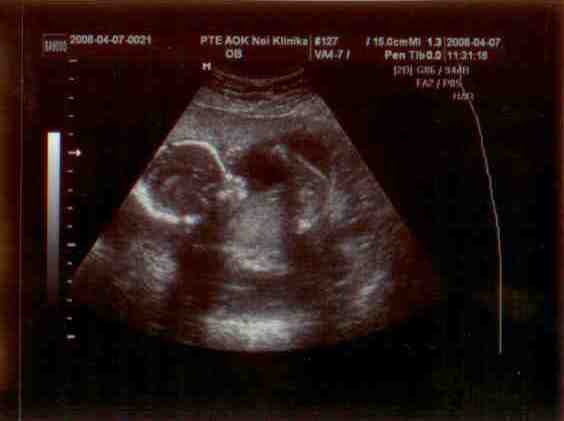

Doki bácsimnál rákukkantottunk Maszatkára, de nem sokat láttunk. elég xar a gép és Baba is elbújt rendesen. Akartam képet kérni és hogy esetleg kukkantsunk már be a lába közé de kb. az volt a válasz, hogy ne kérjek ilyen extrát, örül ha azt látja hogy hogy van bennem a gyerek!

Buksiját tudtuk csak lemérni, aszerint tegnap volt 16+2, tehát teljesen korának megfelelő.